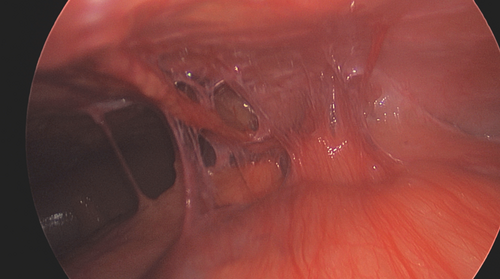

⚠️ Food impaction + normal-ish biopsy ≠ no #EoE.

Mahon et al. show 4 kids with sub-diagnostic eosinophil counts at #EFI who ALL had EoE confirmed on repeat scope. Don't let them fall through the cracks! 👇 #PedsGI #Esophagus #GITwitter